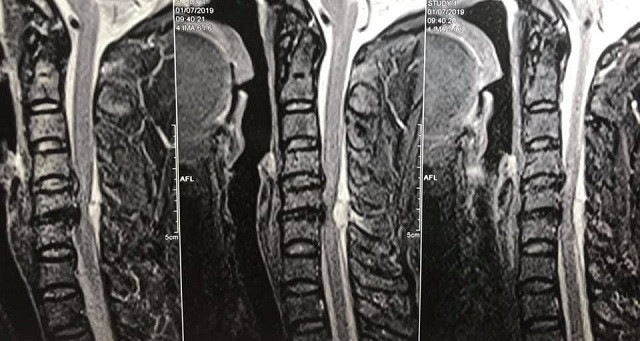

Hình ảnh khối máu tụ rất to chèn ép ống tủy cổ trên phim chụp cộng hưởng từ, nguyên nhân gây liệt cho bệnh nhân.

Gia đình cho bệnh nhân nhập viện tuyến dưới sau đó xin chuyển tuyến lên Bệnh viện Hữu nghị việt Đức. Kết quả chụp cộng hưởng từ cấp cứu tại đây cho thấy, bệnh nhân có một khối máu tụ rất to đang chèn ép nặng cột sống cổ gây ra liệt hai chân.